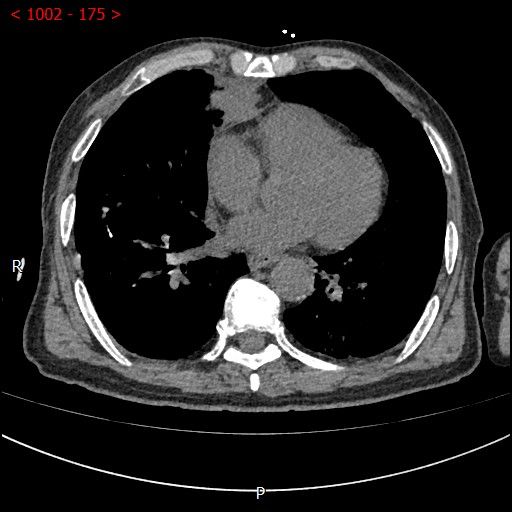

术中影像

男性患者,68岁,检查发现右肺中叶肿块,大小约3.5cm×2.4cm,因患者有慢性支气管炎、肺气肿、肺大泡,基础病较多,无法耐受常规外科手术治疗;经与患者本人及家属多次沟通。血管介入科团队根据患者具体情况决定对该患者施行CT引导下肺肿瘤射频消融术。经全科术前讨论:肿瘤位置毗邻心脏、纵膈、胸膜多处重要器官,手术要求穿刺精准,消融位置精确,尽量避免恶性心率失常,心脏包膜、胸膜、纵膈损伤。经过前期的精心术前准备,2023年7月18日,在血管介入科团队和CT室默契配合下,此次射频消融手术顺利完成。手术全过程仅用时约40分钟,其中消融时间约5分钟。CT观察下见肿瘤形变,周围肺组织呈现“晕”征,提示本次消融范围基本覆盖全肿瘤。术中患者无疼痛并且未产生并发症。本次手术达到杀死肿瘤细胞的同时,最大限度的减少创伤、保留肺组织。